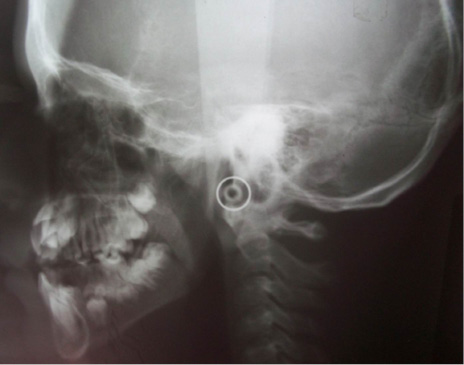

En el estudio imagenológico se observó en la radiografía de tórax, hipoplasia clavicular bilateral y tórax en forma de campana (Figura 2), en la radiografía panorámica se mostró la presencia de once dientes supernumerarios en el maxilar y nueve en la mandíbula (Figura 3), en la radiografía lateral cráneo se observó presencia de huesos wormianos landoideos (Figura 4); en la radiografía carpal se observó longitud simétrica de las falanges y sin alteraciones (Figura 5), de acuerdo con los hallazgos encontrados en el examen físico y la evaluación radiológica, se realizó la impresión diagnóstica de displasia cleidocraneal.

Autores como Paul et al, en 2015 y Forronato et al, en 2009, afirmaron que la radiografía periapical, panorámica, tomografía computarizada y la radiografía de cráneo son herramientas muy útiles para el diagnóstico bucal de la DCC, ya que permiten observar características consideradas patognomónicas para el diagnóstico del síndrome como los múltiples dientes supernumerarios, dientes retenidos y retraso en la osificación de las suturas craneales suturas [1,12]; coincidiendo con el presente caso en el cual el hallazgo radiográfico de alerta encontrado en la ortopantomografía fue la presencia de múltiples supernumerarios localizados en el maxilar y la mandíbula.